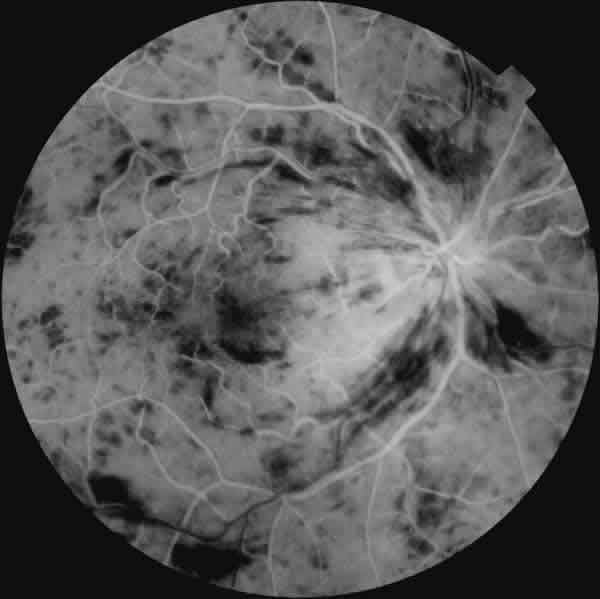

Probablemente la oclusión de vena central de la retina es la patología retiniana en la que el defecto pupilar aferente relativo ha recibido una mayor atención. En este caso resulta útil en el diagnóstico diferencial entre las formas isquémicas y no isquémicas, y por lo tanto su presencia tiene un gran valor pronóstico (fig. 3). El artículo original fue publicado por Hayreh hace más de 20 años (9). En este trabajo, el 90% de los pacientes con una forma no isquémica, presentaban un DPAR de menos de 0,3 unidades logarítmicas, en tanto que el 90% de aquellos que sufrieron una forma isquémica, presentaron un DPAR de al menos 1,2 unidades logarítmicas. El DPAR se convierte de este modo en un método muy sencillo de clasificar inicialmente a estos pacientes. Como resulta fácil de intuir, estudios posteriores han demostrado que presenta una excelente correlación con la angiografía fluoresceínica, la perimetría y el electrorretinograma (10).

Fig. 3: El DPAR resulta de gran utilidad en la clasificación de las oclusiones venosas. En las formas isquémicas está presente un DPAR de alto grado. Por ello tiene un gran valor pronóstico en esta patología.